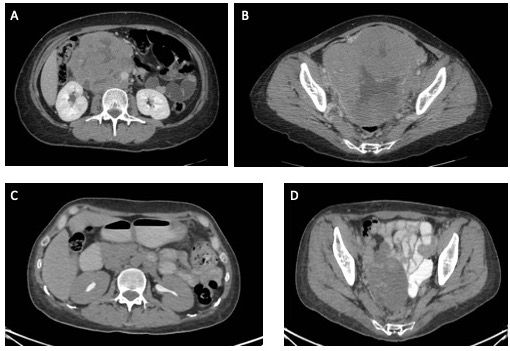

A woman aged 44 years presented at the general oncology outpatient clinic with bloating, abdominal pain, and significant unintended weight loss. Her past medical history included a bilateral inguinal hernia surgical repair at age 6, and primary amenorrhea since age 15. The patient never underwent additional studies to identify the cause of the primary amenorrhea. She resided in a community of low socioeconomic status and completed middle school education. On physical examination, she was phenotypically female, with Tanner stage III-IV breast development and female genitalia with Tanner stage II pubic hair development. A palpable ~10-cm abdominal mass was also found. Complete blood cell count and biochemistry profiles were requested and reported mild normocytic normochromic anemia, without other relevant findings. A CT scan revealed a 10 x 9 cm retroperitoneal tumor, with involvement of the aorta and inferior vena cava; a 16 x 16 cm pelvic tumor in close contact with the common, external, and internal iliac vessels; and absence of uterus and ovaries. There was no evidence of metastatic disease outside the abdomen (Figure 1A/B).

Figure 1: Retroperitoneal (A) and pelvic tumor (B) at diagnosis. Partial response of both tumors after 3 cycles of BEP (C, D).

Option B (good-risk seminoma in a patient with CAIS): Our patient presented as an adult female whose history included inguinal hernia surgical repair before puberty and primary amenorrhea that had not been investigated since puberty. The patient suffered from bloating, abdominal pain, and significant unintended weight loss as well as a palpable abdominal mass on physical examination. The patient’s female phenotype mismatched the results of karyotyping (46,XY). CT scan revealed a 10 x 9 cm retroperitoneal tumor and a 16 x 16 cm pelvic tumor (undescended testes), in addition to absent uterus and ovaries. In our case, the clinical picture in addition to karyotyping results (46,XY), CT findings, the elevated testosterone, the elevated tumor markers (LDH, AFP, hCG), as well as the histopathological analysis of the pelvic tumor biopsy altogether confirm a germinomatous GCT (seminoma) in a patient with a CAIS. Therefore, option B is the correct answer.

The patient received 3 cycles of combination chemotherapy with bleomycin, etoposide and cisplatin. Tumor markers normalized and a PET/CT scan showed partial response (–34% reduction in size) by RECIST criteria (Figure 4A/B). The patient underwent a laparotomy for resection of the pelvic tumor and retroperitoneal lymphadenectomy. The pelvic tumor corresponded to a prepuberal necrotic testis (Figure 5A/B).Whilethe retroperitoneal tumor could not be completely resected, pathology results showed xanthogranulomatous necrosis and no evidence of malignant cells in either the pelvic tumor or the partially resected retroperitoneal tumor, consistent with a complete pathological response. The contralateral gonad was also resected, corresponding to atrophic prepuberal testis (Figure 5C/D). The patient received external beam radiotherapy (36 Gy) to the remaining retroperitoneal lesion, with further reduction in the size of the lesion. The patient is alive and well, without clinical evidence of disease, 8 months after the surgery. Since the patient had a residual mass after completion of radiotherapy, in her first year of follow-up she has undergone tumor marker testing and CT imaging every 2 months, without any evidence of recurrence.